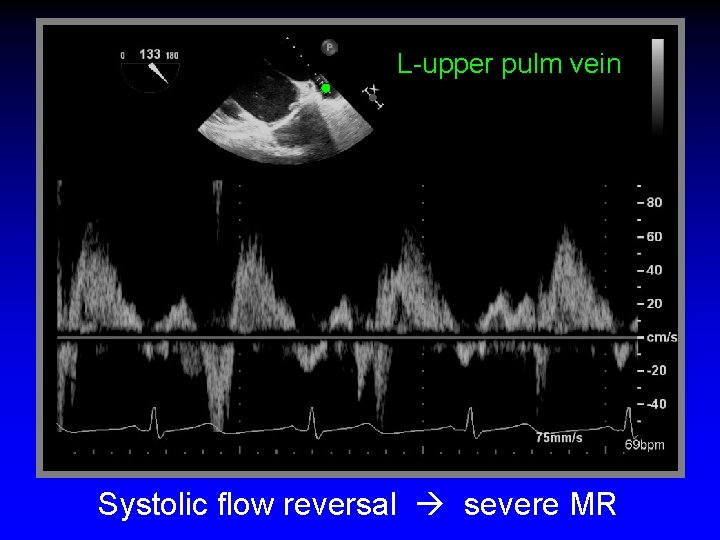

L-upper pulm vein Systolic flow reversal severe MR